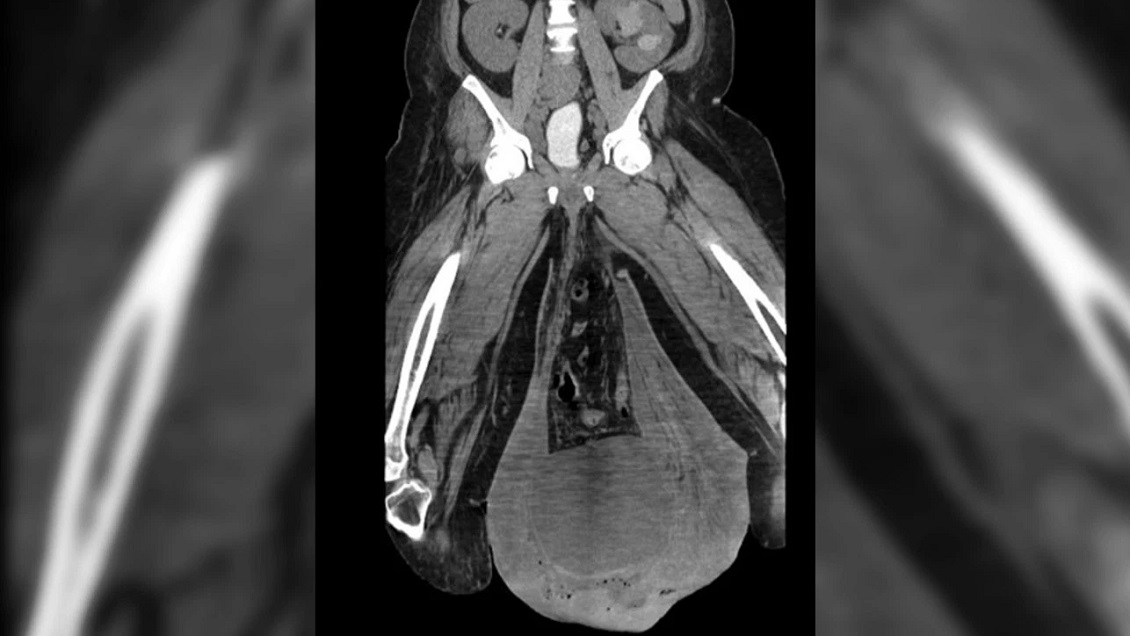

Un hombre de 43 años fue víctima de un extraño caso médico en que sus testículos se hincharon al punto de quedar del tamaño de pelotas de fútbol o de básquetbol.

El hombre había sido hospitalizado con fiebre y dolores cuando reveló su preocupante hinchazón: su escroto pesaba más de 3 kilos y le impedía hacer cualquier cosa con normalidad.

Los médicos determinaron que tenía una grave infección bacterial en los genitales debido a mala higiene.